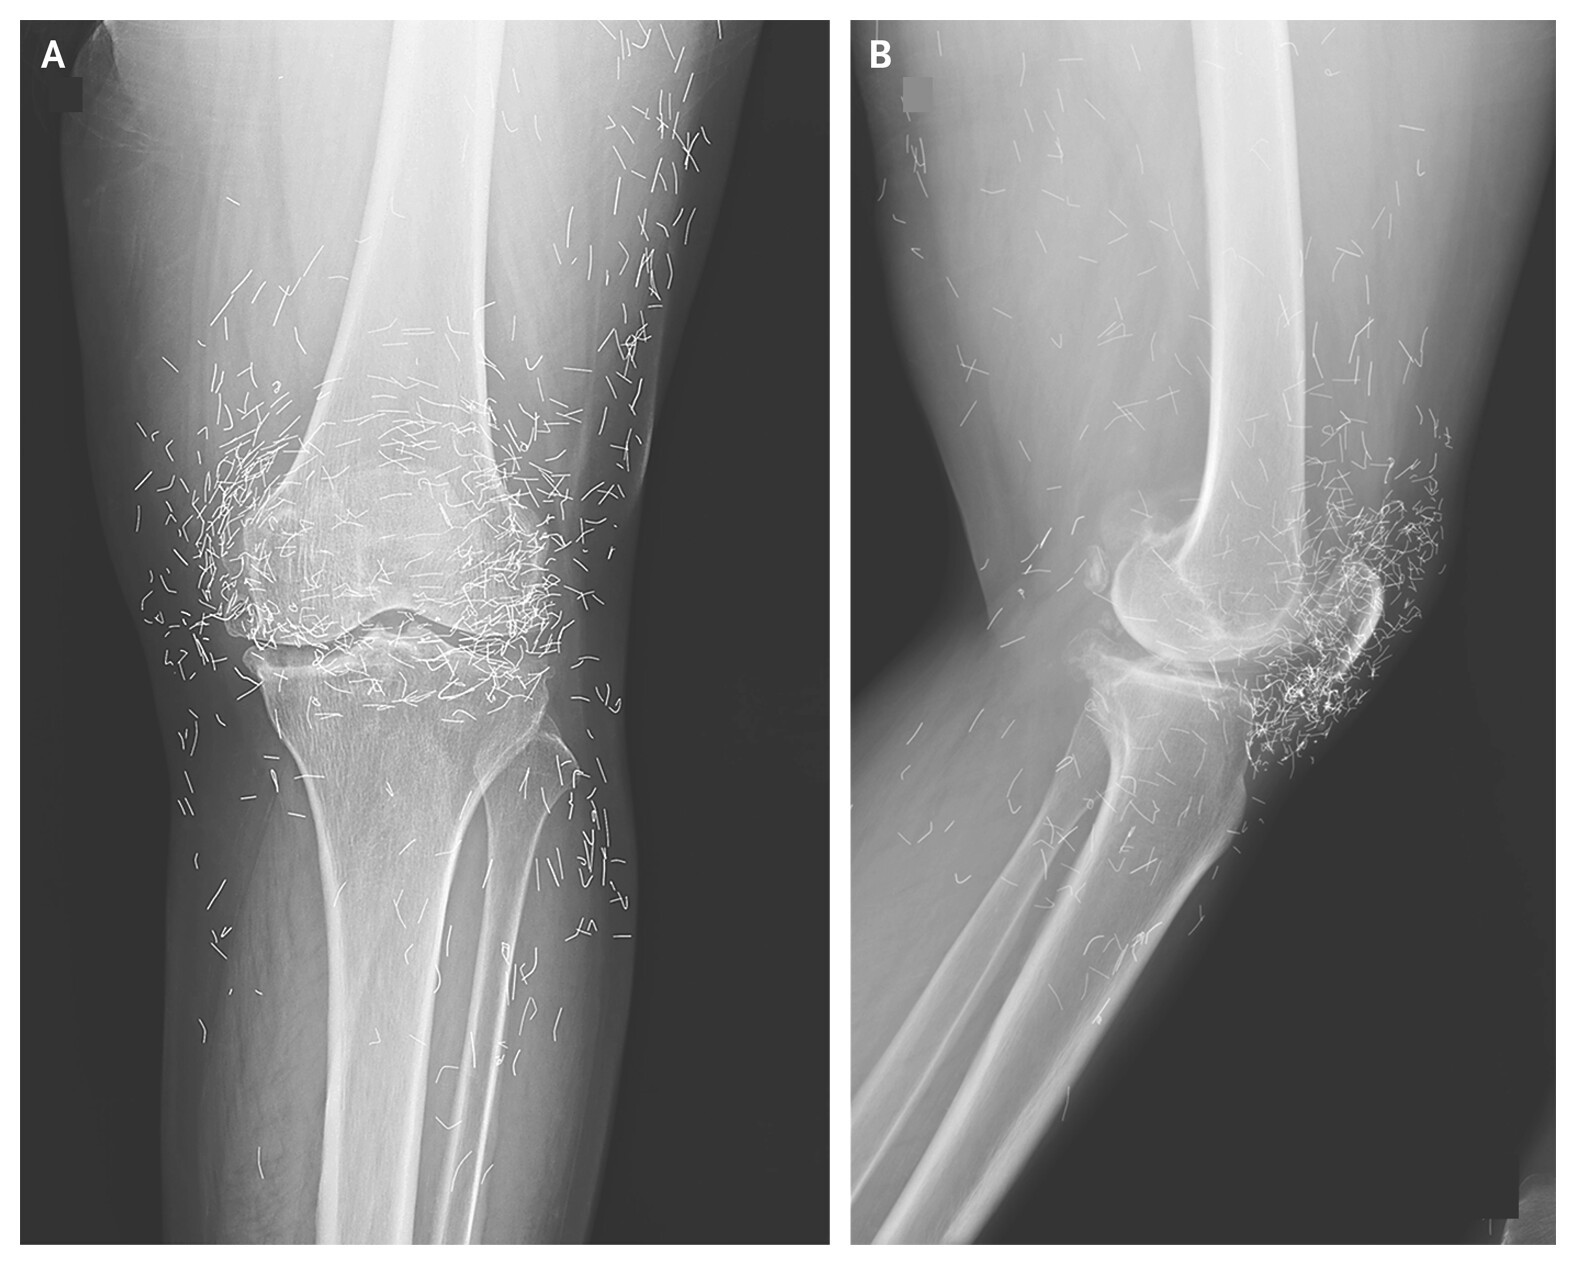

Caso foi descrito em periódico médico e expõe os riscos de terapias alternativas que prometem aliviar dor, mas podem agravar doenças como a osteoa...